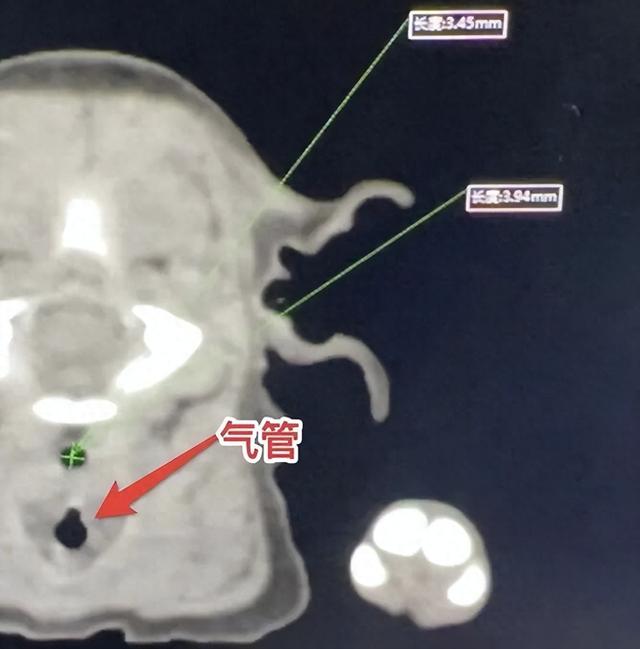

此次动物实验,按照实验研究方案选取体重分别为2.5kg、3kg、5kg三只与新生儿食管闭锁手术患儿体重和月龄相近的巴马小型猪(Bama Mini-Pig)作为实验对象,在全麻下对三只实验动物实施心电、血氧、血压及血气指标的监测。术中首先切除3cm胸腔段食管建立食管闭锁动物模型。第一只经开放手术顺利完成食管替代吻合,随后的第二、第三只小猪先后采用胸腔镜微创手术非常顺利地进行应用高分子支架材料的食道重建手术,成功一期修复了3cm的食道缺损。手术结束三只实验动物均获存活。同时,术前通过CT明确该年龄段实验动物的食管内外径,填补了该方向的数据空白。这一成功,为后续开展的临床研究奠定了坚实的基础。

术前CT显示实验动物食管